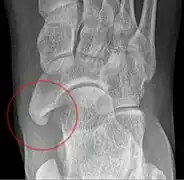

Images radiologiques

De gauche à droite : types 1, 2 et 3

Type 2 sur un pied (flèche sombre) et type 3 sur l'autre (flèche blanche)